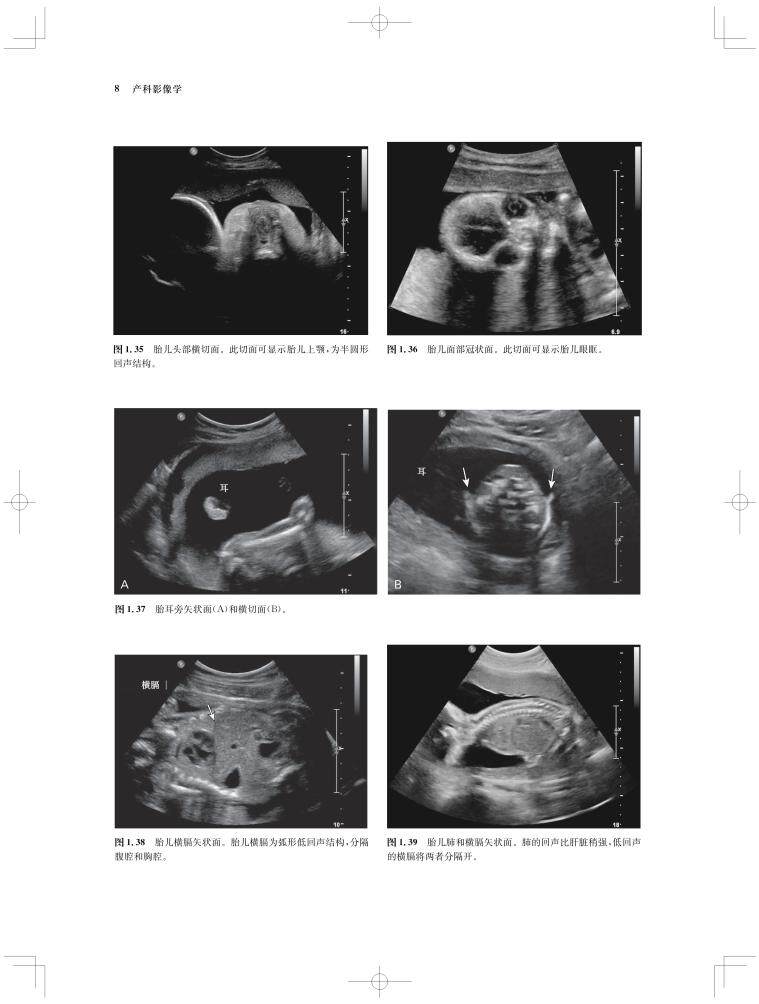

内容涵盖了胎儿宫内疾病的所有病种,从疾病的概述、流行病学、病因学、病理生理学,到临床表现、各类影像学技术的诊断和鉴别诊断,再到产前、产后的治疗和干预手段,都做了全面介绍,重点阐述了疾病的超声、X线、CT、MRI、PET、CT等影像学表现,以及诊断与鉴别诊断,并辅以大量标准化的影像学图片,图文并茂。

《产科影像学——胎儿诊断和监护》是Elsevier(Saunders)出版的“Expert Series”之一,由国际最顶尖的妇产科、生殖科、母胎医学和影像学专家共同编写,代表着该领域最顶尖的水平。书中配有大量典型影像图片,内容丰富全面,编写理念先进,侧重于疾病的影像学征象分析及鉴别诊断和诊断流程的制定,从临床思维上进行了更新;同时兼顾临床和病理医师,重点内容以列表、提要、要点的形式进行总结,提纲挈领,方便读者阅读、记忆。对于每天不断进行诊断与鉴别胎儿疾病的影像工作者、病理科和临床医师而言,具有重要的参考价值。